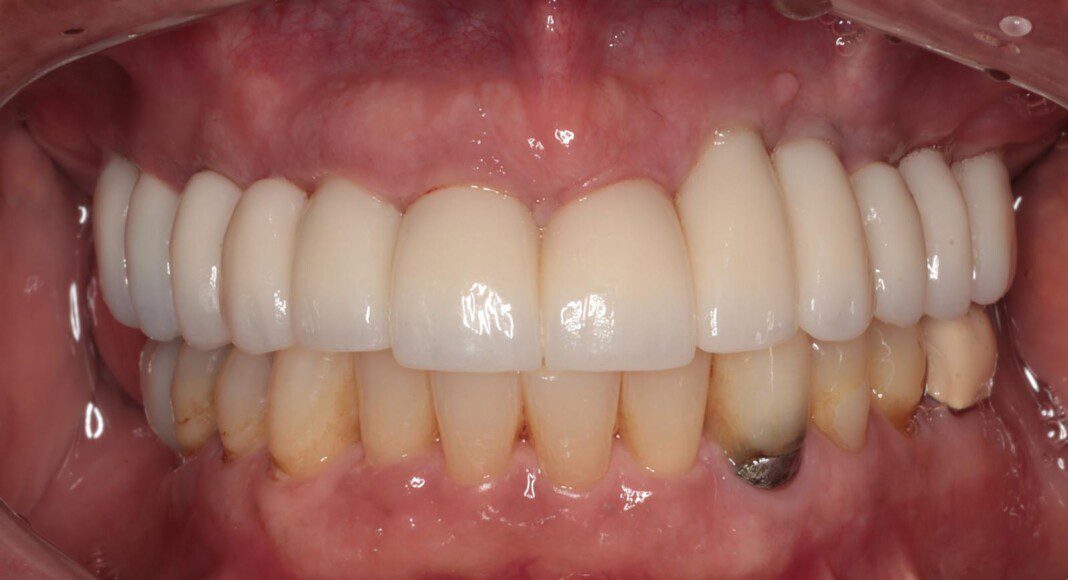

Prototype try-in. This patient was much more particular than we expected. Therefore, we made a very detailed prototype for everyone to evaluate closely. Pictures taken from all angles.